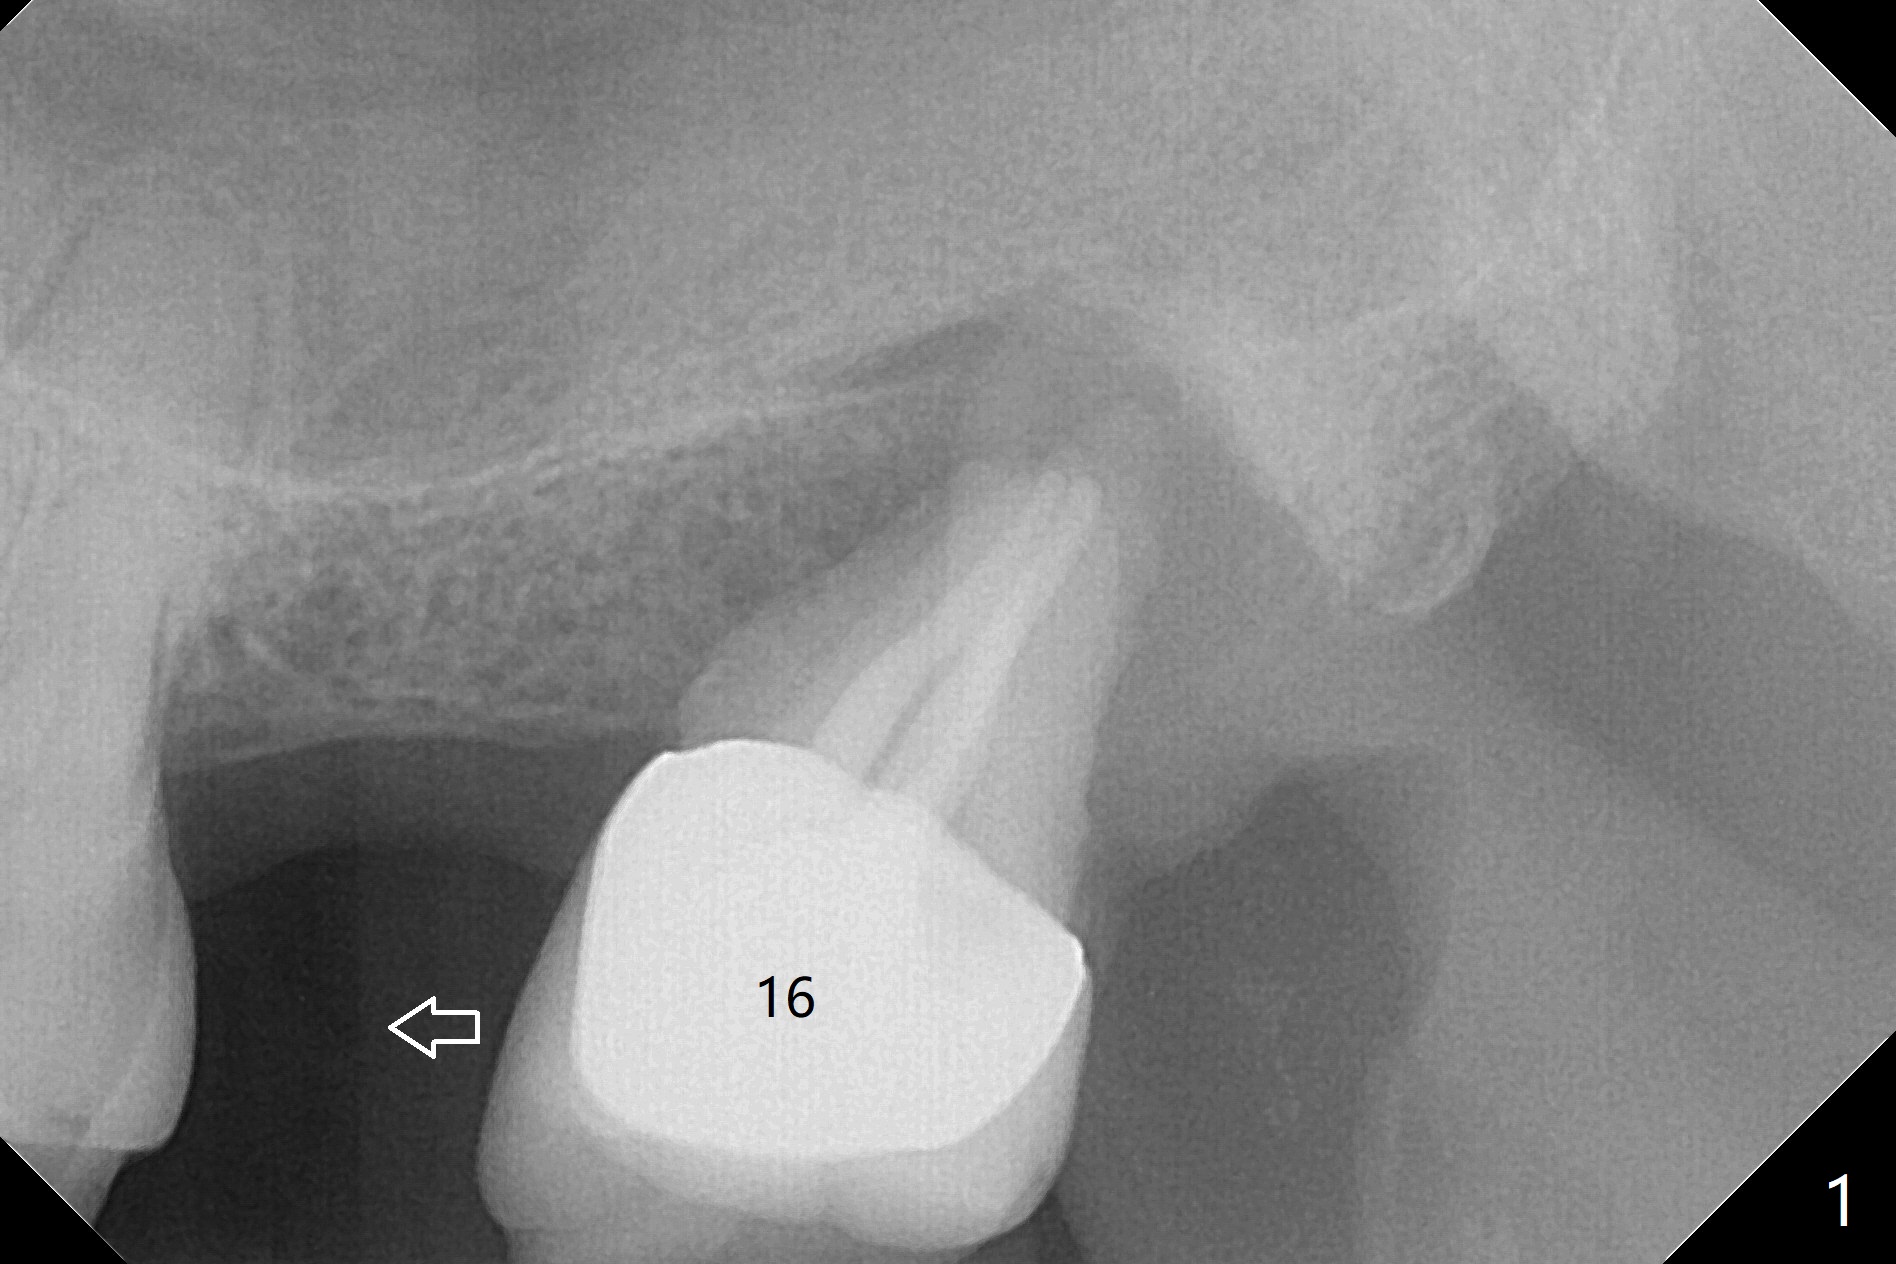

68岁男,缺失15号牙,由单颗牙局部托牙修复。当16号牙松动,近中移位,病人考虑拔除16号牙,经过讨论他同意在15号牙种植,治疗计划(图一)?17,18号牙存在。最佳方案:16号牙拔除(图一’:黑色),同期15号牙种植(绿色)。不过病人马上要出差,只好先拔牙(第二方案),需要植骨(图一”:圆圈)?其实需要植骨(图二:*),因为16号牙牙槽窝(图三:红虚线)侵犯15号牙植牙区(绿色)。植骨减少后期种植,植体螺纹远中螺纹暴露。